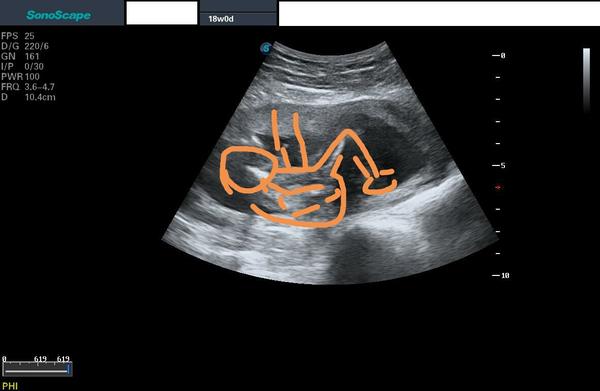

Zkusila jsem to nacrtnout v mobilu, moc to nejde :D

Ja bych rekla lezici miminko, vlevo hlavicka, to vyrazny rucicky, takovy to vroubkovany nahoru pupecnik a pak nozky 🙂

Jak rika @petruuushkaaa 🙂 presne, levo hlavicka, pak kousek doprava rucicka a pokrcena nozicka tvar ^ 🙂